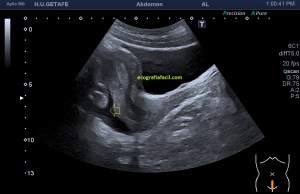

Durante la exploración de una eco de abdomen en el contexto de un paciente que acude por elevación de transaminasas observo una imagen heterogénea, irregular, con una pared marcadamente calcificada, bilobulada de gran tamaño que medí en dos partes ya que me pareció claramente que estaban diferenciadas.

Una de ellas, la primera, era mucho más hiperecogénica y más pequeña, su centro estaba mas calcificado, su sombra acústica posterior era mucho más acuciada y llamaba más la atención. Justo al lado, otra lesión de mayor tamaño, su calcificación era mucho más sutil y más periférica delimitando una LOE hipoecogénica de un tamaño muy importante, adyacente a la más pequeña, como he comentado previamente. Ambas sin señal Doppler.